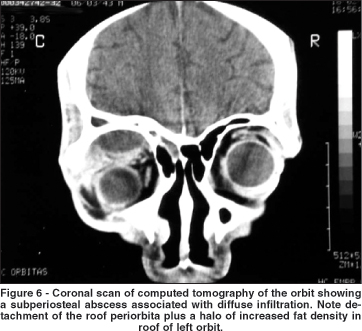

In order to categorize the radiological patterns of cellulitis the following guidelines were adopted. Diffuse fat infiltration was characterized by an increased density of the extra- or intraconal fat. The limits of the transition between the normal fat and the enhanced fat density were typically gradual and not well defined. A subperiosteal abscess was diagnosed when the periorbita was elevated from at least one orbital wall adjacent to a paranasal sinus. Finally, an orbital abscess was defined whenever an abnormal heterogeneous density was found (with or without ring appearance) within the orbital fat.

In all cases intraorbital changes could be detected. Diffuse infiltration was seen as an isolated feature in 11 patients (24.44%) who were successfully managed using medical treatment with intravenous antibiotics alone (Figure 4). As shown in Figure 5, subperiosteal abscesses were diagnosed in 28 patients (62.23%). The detached periosteum was usually well demarcated, defining the border of fluid collection. In 9 patients (20%) there was a diffuse fat infiltration at the boundaries of periorbita elevation (Figure 6). Orbital abscesses were seen in 6 patients (13.33%, Figure 7). All of these cases were surgically confirmed.

Subperiosteal abscesses can also lead to intracranial complications and to visual impairment(37-38). However, this condition has distinct characteristics. The fluid collection is limited by the periorbita with varying amounts of fat infiltration beyond the well demarcated border of the detached periorbita. It is well known that in some cases of periorbita detachment there is no pus between the bone wall and the periorbita, the periosteum elevation being caused by hemorrhagic or clear fluid and edema(39).